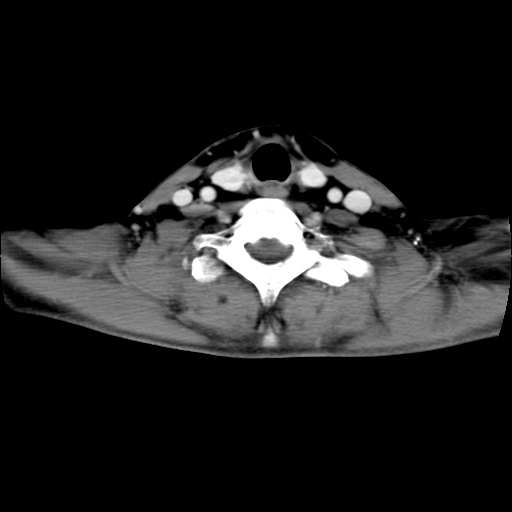

标题: CT24019:男,45岁,发现颈部肿物5个月。 [打印本页]

男,45岁,发现颈部肿物5个月,彩超示:双侧颈部及下颌部软组织增厚。

考虑双侧颈项部良性对称性脂肪增多症。

双侧颈项部脂肪沉积